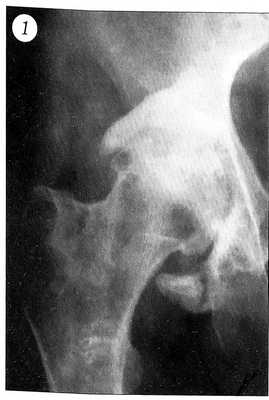

При прогрессировании процесса рентгенологическое обследование выявляет грубую деформацию вертлужной впадины, нарушение ее пространственной ориентации. Головка бедренной кости находится глубоко во впадине. Суставная щель резко сужена или отсутствует вследствие разрушения и дегенерации покровного хряща сочленяющихся поверхностей. Структура головки бедренной кости характеризуется склерозированием ее по сегментарному или тотальному типу. Со стороны краев вертлужной впадины формируются костно-хрящевые выросты треугольной формы, которые наподобие панциря покрывают шейку бедра, приближаясь к основанию большого вертела. Отчетливо определяется нижний край вертлужной впадины, который окружает головку бедра снизу, переходя на шейку (рис. 1).

Рис. 1. Рентгенограмма правого тазобедренного сустава больного с посттравматической протрузией вертлужной впадины.